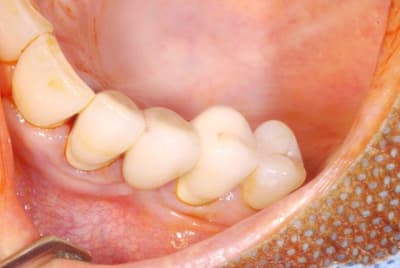

pour débuter ce post je propose un petit cas avec une ROG un comblement alvéolaire et un lambeau pédiculé pour fermer le site d'extraction.

je suis bien curieux de connaître quels sont vos protocoles lors d'une extraction.

proposez vous comme moi systématiquement un comblement osseux ou une chir pour fermer hermétiquement la plaie?

faites vous dans la foulée de l'extraction une ROG ou la mise en place d'une membrane ??